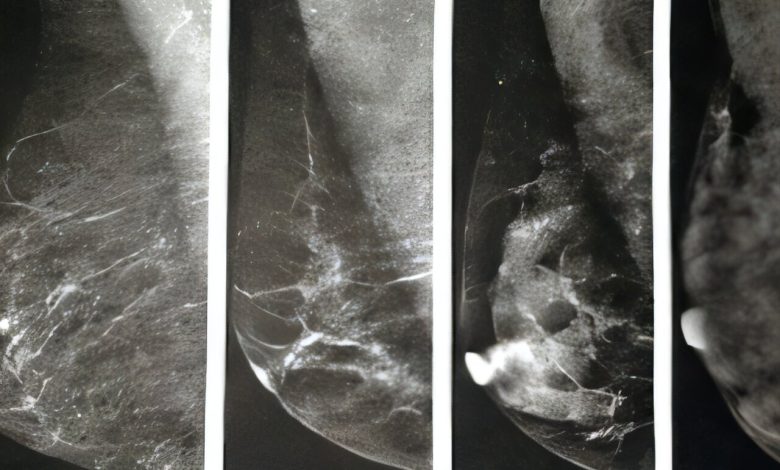

Essas varreduras de raios X mostram as quatro categorias de densidade mamária. As duas imagens à esquerda são consideradas “não densas” e as duas à direita são consideradas “densas”. Crédito: UT Southwestern Medical Center

Os seios contêm três tipos principais de tecido: tecido glandular, conjuntivo fibroso e tecido adiposo. O tecido adiposo aparece escuro na mamografia, enquanto os tecidos conjuntivos glandulares e fibrosos aparecem brancos. O problema é que os tumores também aparecem brancos, dificultando a identificação do que é tecido mamário normal e do que pode ser câncer.

Seios densos apresentam maior quantidade de tecido conjuntivo glandular e fibroso e menor quantidade de tecido adiposo. A densidade mamária é classificada em quatro categorias usando o sistema BI-RADS do American College of Radiology:

- Tecido mamário totalmente gorduroso: seus seios são compostos de quase todo tecido adiposo. Cerca de 10% das mulheres têm esse tipo.

- Tecido mamário fibroglandular disperso: Você tem principalmente tecido adiposo com algumas áreas densas de tecido conjuntivo glandular e fibroso. Cerca de 40% das mulheres têm esse tipo.

- Tecido mamário heterogeneamente denso: você tem muitas áreas de tecido conjuntivo glandular e fibroso com menos áreas de tecido adiposo. Cerca de 40% das mulheres têm esse tipo.

- Tecido mamário extremamente denso: você tem quase inteiramente tecido conjuntivo glandular e fibroso. Cerca de 10% das mulheres estão nesta categoria e enfrentam um risco ligeiramente maior de cancro da mama; mais pesquisas são necessárias para entender o porquê.

As mulheres dos dois últimos grupos são consideradas como tendo “seios densos”.

Se você tiver tecido mamário fibroglandular totalmente gorduroso ou disperso, verá “não denso” em seus resultados. Se você tiver tecido mamário heterogêneo ou extremamente denso, verá “denso” em seus resultados.